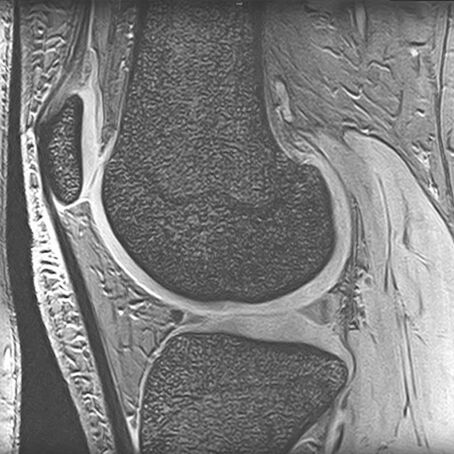

Magnetresonanztomographie (MRT, Kernspintomographie)

MRI eines Kniegelenks, zeigt Knochen- und Gewebestrukturen seitlich im Querschnitt.

Die Magnetresonanztomographie stellt sämtliche Körperregionen überlagerungsfrei dar. Das Magnetfeld ist für den menschlichen Körper ungefährlich. Die Magnetresonanztomographie ist ambulant wegen des exzellenten Gewebekontrastes das wichtigste röntgenstrahlenfreie radiologische Diagnoseverfahren.